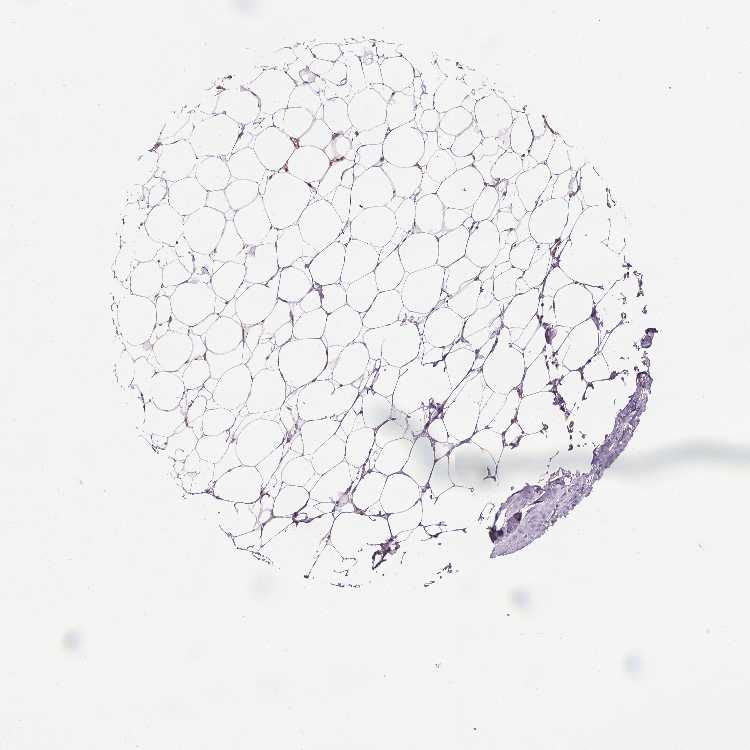

BREAST - Antibody stainingi

Antibody staining in the annotated cell types in the current human tissue is reported as not detected, low, medium, or high, based on conventional immunohistochemistry profiling in selected tissues. This score is based on the combination of the staining intensity and fraction of stained cells.

Each image is clickable and will lead to virtual microscopy that enables deeper exploration of all samples and also displays staining intensity scores, fraction scores and subcellular localization as well as patient and tissue information for each sample.

Antibody HPA065425Antibody CAB069426

Adipocytes Not detectedNot detected

Glandular cells MediumMedium

Myoepithelial cells MediumLow